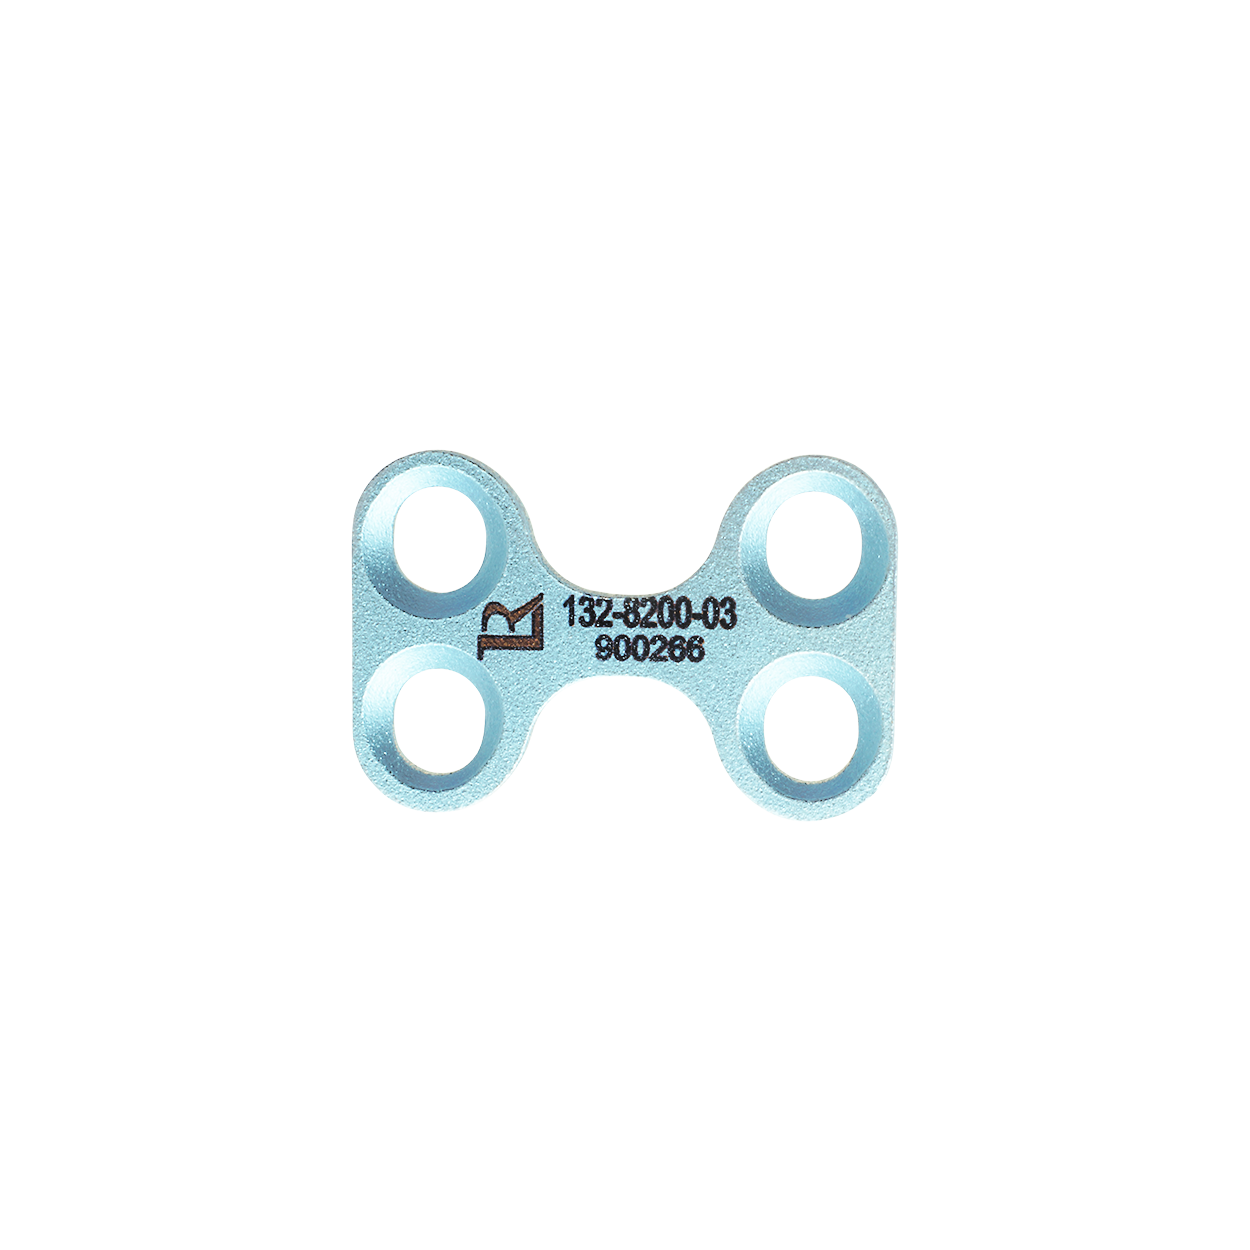

The RAPID Patella Luxation Plates and Spacers constitute a versatile system designed to address patellar luxation across a diverse range of patient sizes and breeds.

Offering three different plate sizes (Petite/Tiny 2.0 mm, Medium 2.4 mm, Large 2.4 mm), and a total of 20 different spacer variations to match the plates, the RAPID Luxation System enables the surgeon to select the appropriate plate and spacer combination to address the unique anatomical challenges presented by each patient.

The RAPID Luxation Implants and Screws are made of medical grade Titanium for best biocompatibility.

Designed to fit together seamlessly, the RAPID Luxation Plate and Spacer are securely fixed together to the bone by screws, preventing unwanted movement and ensuring stability and alignment of the patella within the trochlear groove. This allows for uninterrupted bone growth and integration, facilitating a rapid recovery process.

The versatility of the system also allows for a re-correction of the patellar alignment post-operatively, which may be necessary in some cases. Instead of performing a complex revision surgery, orthopedic surgeons can simply replace the spacer with another size as needed. This streamlined process reduces surgical trauma and recovery time for the patient while effectively addressing any residual luxation or malalignment, ensuring optimal long-term joint function.